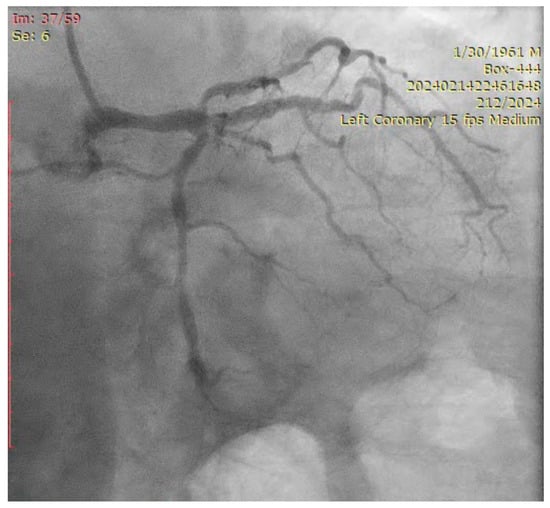

- Engage the left coronary artery with an EBU 4.0/8F guiding catheter. Wiring the three branches of the trifurcation (Floppy guide wires in LAD and RI, Hydrophilic guide wire in LCX) (Figure 14).